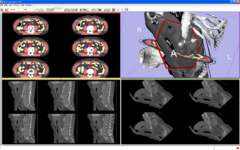

The Lightbox: Functionality for displaying cross-sectional data in columns and rows.